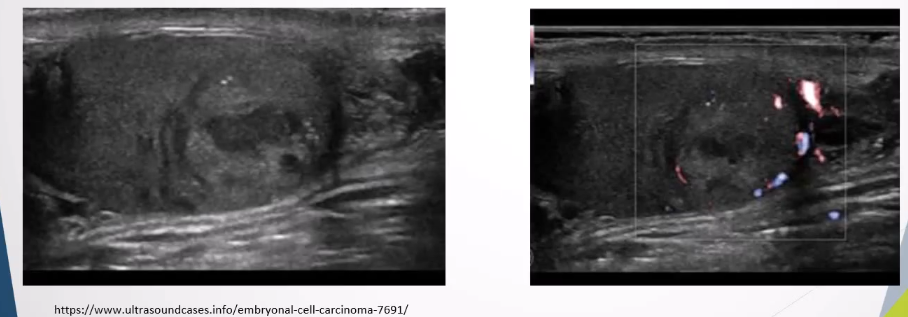

Ultrasound Appearance: Homogeneous intratesticular mass, well-circumscribed with lobulated margins, internal vascularity

Non-seminomas: Occur mainly in younger patients, more aggressive, and metastasize frequently.

Clinical Presentation: Similar to seminomas with potential for metastasis.

Ultrasound Appearance: More heterogeneous with cystic areas or calcification.